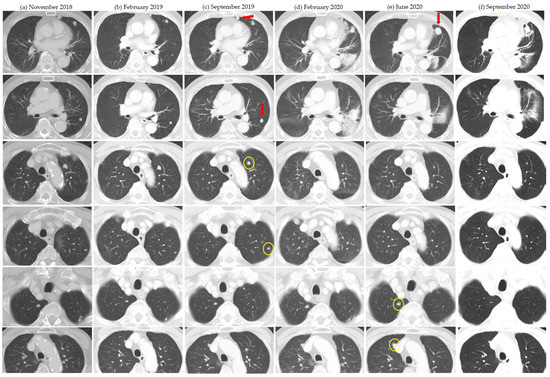

| 3 | Ipilimumab + Nivolumab | 10 14 | 36Gy/3 30Gy/5 | Yes Yes | Lung Adrenal | Lung, 2 Lung, 1 | 2 5 | 1 tumor with abscopal response after initial enlargement post SBRT 4 |

| 6 | Nivolumab | 17 26 | 54Gy/3 42Gy/5 25Gy/5 | Yes Yes | Lung Lung | Lung, 2 Lung, 2 | 5 3 | Prior spontaneous regression and dissociated response after cytoreductive nephrectomy |